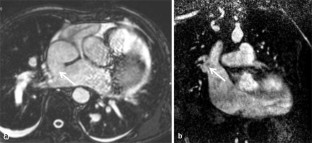

Abb. 3

23. Desch S, Eitel I, De Waha S et al (2011) Cardiac magnetic resonance imaging parameters as surrogate endpoints in clinical trials of acute myocardial infarction. Trials 12:e204–e215